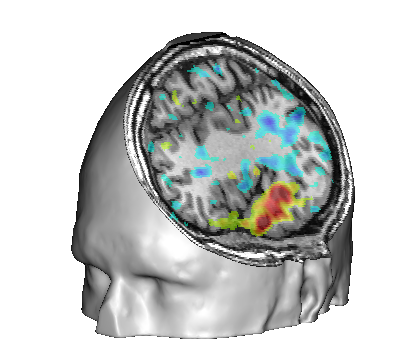

Fusion between an anatomical volume and an activation map

Load:

T1 MRI:

data_for_anatomist/subject01/subject01.niiActivation map:

data_for_anatomist/subject01/Audio-Video_T_map.nii

Fusion the 2 images. Note that they are not well superimposed because they are not in the same referential. But they are in Nifti format and contain information about a transformation to the referential Talairach-MNI Template-SPM.

For each volume, right-click Referential => Load information from file header.

Look at the fusion, the 2 images are now well superimposed.

Change the point of view by changing the referential of the window: click on the colored bar at the top of the window and choose Talairach-MNI Template-SPM. Notice the change of orientation.

Fusion between an activation map and a T1 MRI¶